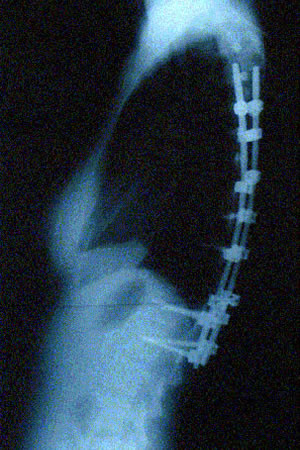

Grafilerle Skolyoz